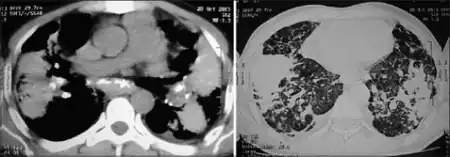

| Coalescence of nodules, lung parenchyma became fibrotic with appearance of bilateral conglomerated mass lesion, this confluent and consolidated shadow is indicative of progressive massive fibrosis | |

Progressive massive fibrosis (or Complicated pneumoconiosis[1]), characterized by the development of large conglomerate masses of dense fibrosis (usually in the upper lung zones), can complicate silicosis[2] and coal worker's pneumoconiosis.[3] Conglomerate masses may also occur in other pneumoconioses, such as talcosis,[4] berylliosis (CBD),[4] kaolin pneumoconiosis,[5] and pneumoconiosis from carbon compounds,[5] such as carbon black, graphite, and oil shale. Conglomerate masses can also develop in sarcoidosis,[6] but usually near the hilae and with surrounding paracicatricial emphysema.